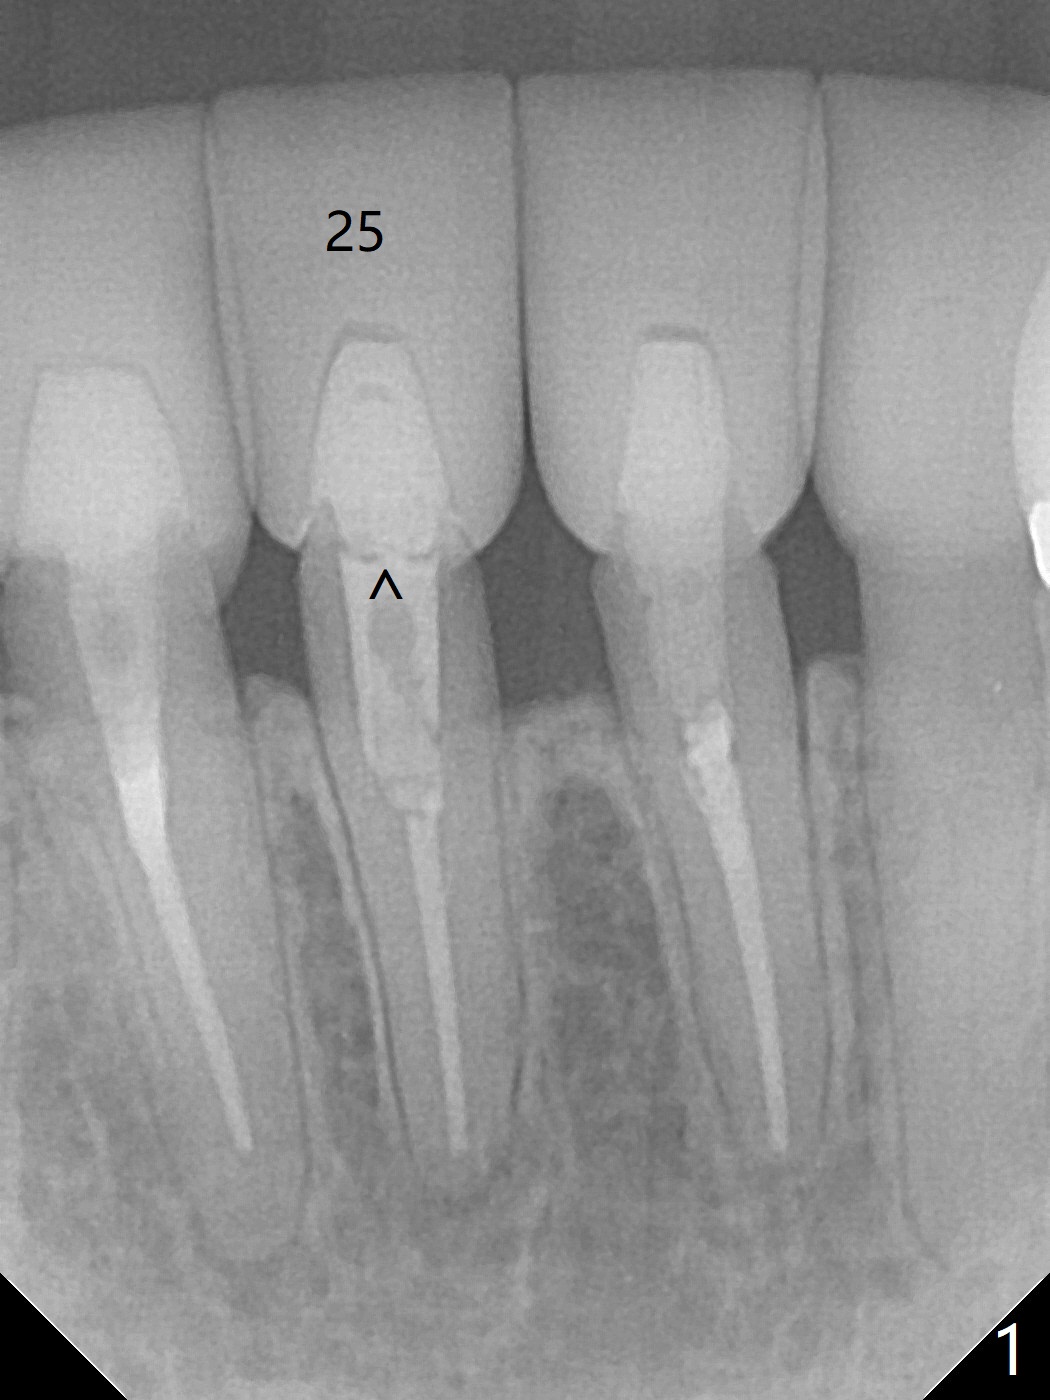

A drawback of implant planning at #25 is not to use a preop PA (Fig.1 (^ fracture line)). The initial trajectory seems to be alright (Fig.2), but a 2.5x14(2) mm implant placed is close to the tooth #26 (Fig.3). In fact the affected tooth is deviated distal; osteotomy should be initiated in the mesial slope of the socket (Fig.4 red line). The final trajectory appears to be perfect (Fig.5). Furthermore the 1st intraop PA should be analyzed carefully (Fig.6). A new osteotomy should be established mesial or the existing one should be moved mesial with Lindamann bur (Fig.7). The distal implant placement may be related to more bone loss in the distal crest 3.5 months postop (Fig.8) and more severe distal papillary recession (Fig.9 *). The bone density increases at the levels of the non-thread and thread portions of the implant (in the original socket) nearly 10 months post cementation (Fig.11 *, <). There is no bone loss 16 months post cementation (Fig.12).